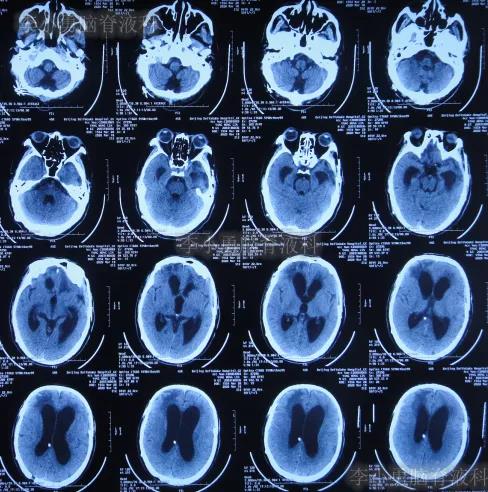

2019年10月20日患者骑电动车在马路上行驶时被大货车撞倒,当时意识清楚,只感到有些头晕,未在意就自行回家,但回家后约3-4小时出现头晕加重,并伴有恶心呕吐的症状,家人急送到当地的河北省邯郸市某医院,查头颅CT示脑出血(图-1);既往病史2015年曾因头部外伤致硬膜下血肿,进行了钻孔引流术。

图-1:2019年10月20日头颅CT